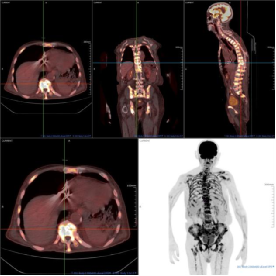

影像学佐证

(附PET/CT图像:前列腺前部正中局灶性高代谢灶SUVmax6.80、全身骨骼多发高代谢灶及纵隔及肺门多发淋巴结异常摄取。)